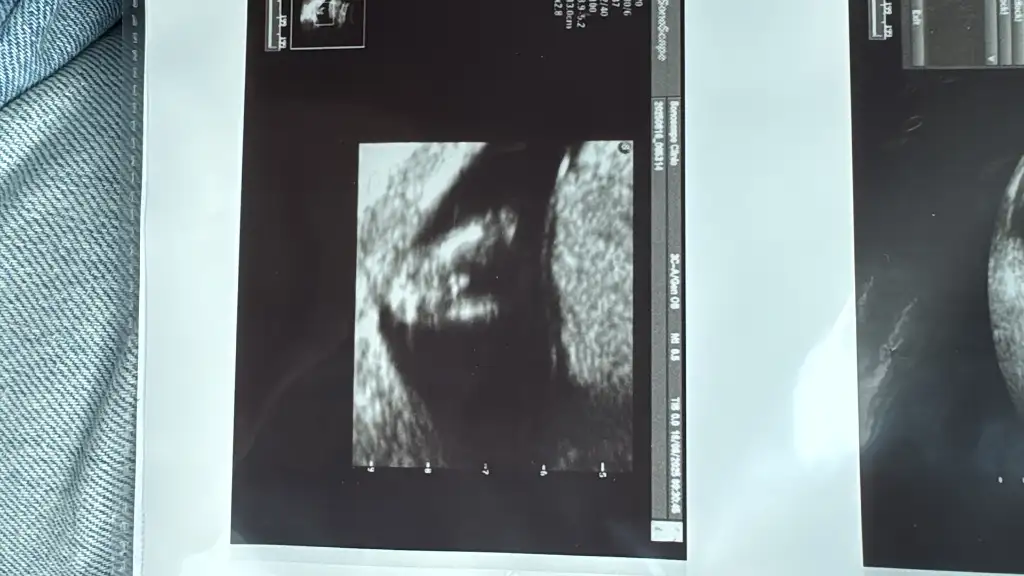

Cinsiyet tahmini yapar mısınız ?

Ben sadece ilk gebeligim oldugu icin merak ediyorum 13 haftalık lütfen yaa tahmin edin

13 haftalık bebeğin neresinden anlayalım

Kaldı ki benim bebeğime 17 haftaya kadar kız dediler de sonra erkek oldu. Doktorların yanıldığı yerde biz nasıl bilelim